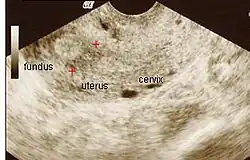

HSG showing filling defects at the adhesion sites. Additionally, this uterus appears to be T-shaped.

The history of a pregnancy event followed by a D&C leading to secondary amenorrhea or hypomenorrhea is typical. Hysteroscopy is the gold standard for diagnosis.[18] Imaging by sonohysterography or hysterosalpingography will reveal the extent of the scar formation. Ultrasound is not a reliable method of diagnosing Asherman's Syndrome. Hormone studies show normal levels consistent with reproductive function.